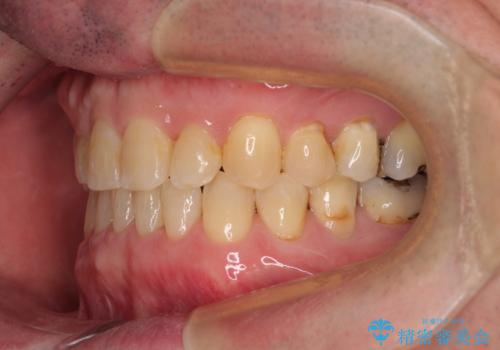

インプラント埋入による仮歯の装着や、前歯の反対咬合の改善は比較的スムーズに達成されましたが、舌突出癖などの影響による、歯列全体のスペースを閉じることが難航し、期間がかかってしまいました。

治療後も舌突出癖が残っていると、あっという間にスペースができてしまうので、トレーニングを継続するように指導をしています。